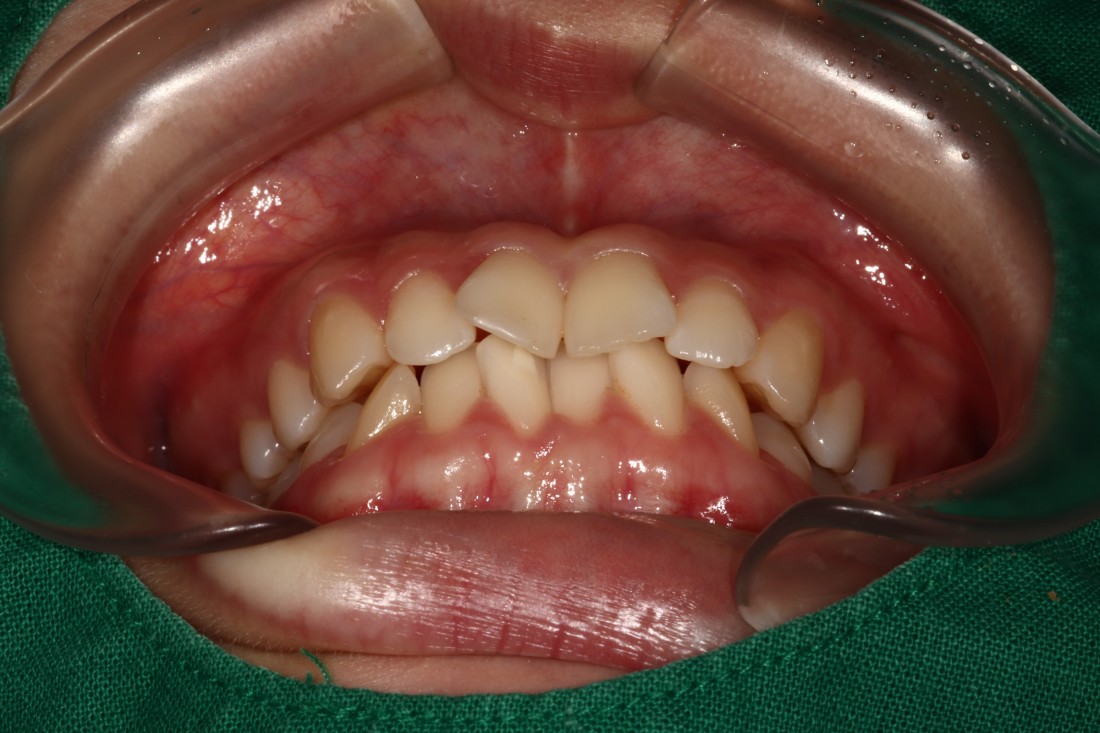

발치교정, 비발치교정을 결정하는 것은

교정 전 3차원 105항목 정밀검사를 통해

교정전문의 대표원장님과의

세심한 상담을 통해 정하게 됩니다.

무조건 비발치 교정만이 좋은 것은 아니며,

개인차에 의해 발치교정이 필요한 경우에는

발치교정을 통해 원하는 교정치료 결과를

얻을 수 있습니다.